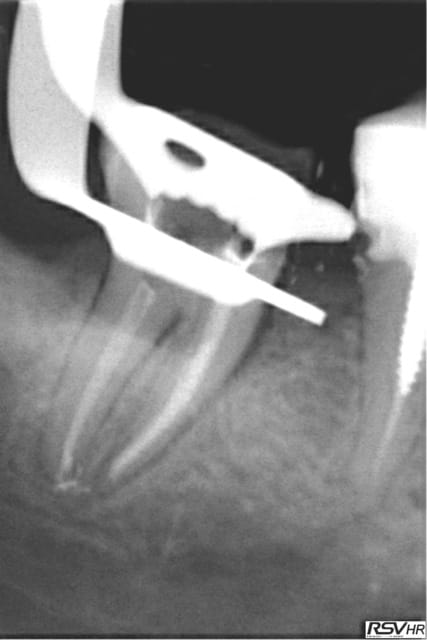

Tiens les endos de la semaine, que d'apex défoncés !-))

La 47 en fin le distal est obturé au système B (bouchon apical) et au mac spaden pour la partie coronaire, tu vois la différence à la radio ? Alors l'apex défoncé il faut avoir l'oeil ! peut etre mais à 25 centièmes et à conicité 6 %........-))